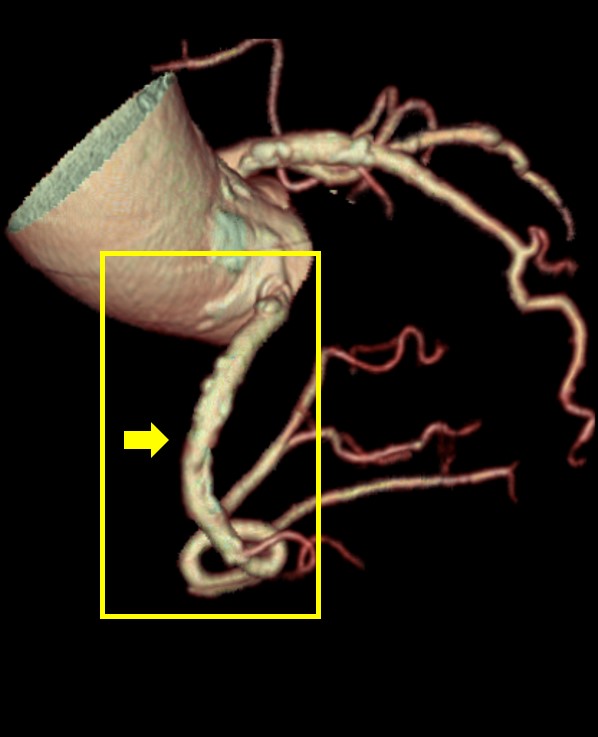

TAVI術前検査における活用例

下記の画像は、TAVI術前検査のAf症例ですが、このデータでも不整脈や石灰化があるにも関わらず弁に対して十分な画像が得られており、列数の影響を感じさせない画像が提供することができました。

循環器医師からも、「64列装置でも十分評価できているね!」と言っていただけるほど、評価が高かったことが印象的です。

Ascend_ayase04.jpgTAVI術前検査でのSSF2.0処理後の画像